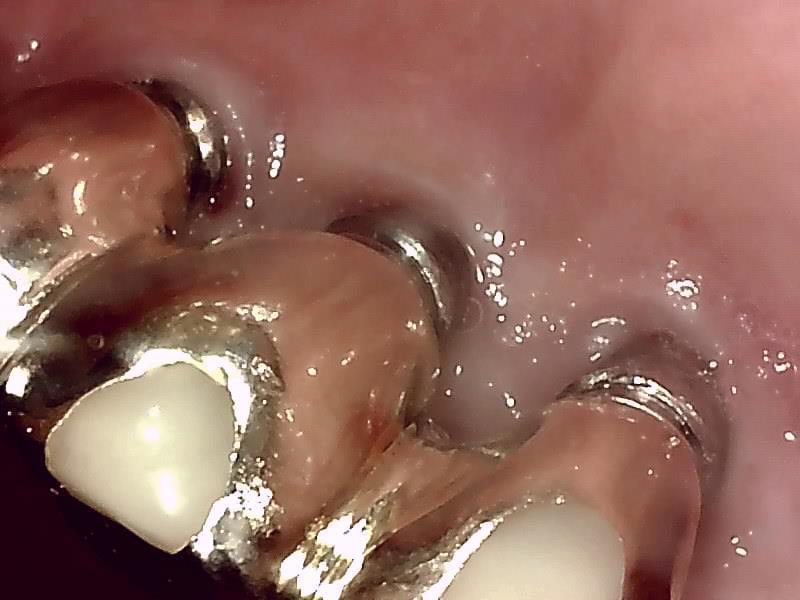

写真の症例はインプラントから膿がでています。

本症例はインプラントを消毒しても治らなかったので、インプラントのバイ菌を除去する手術で

なおさせていただき、歯ぐきはしっかりと引き締まりました。